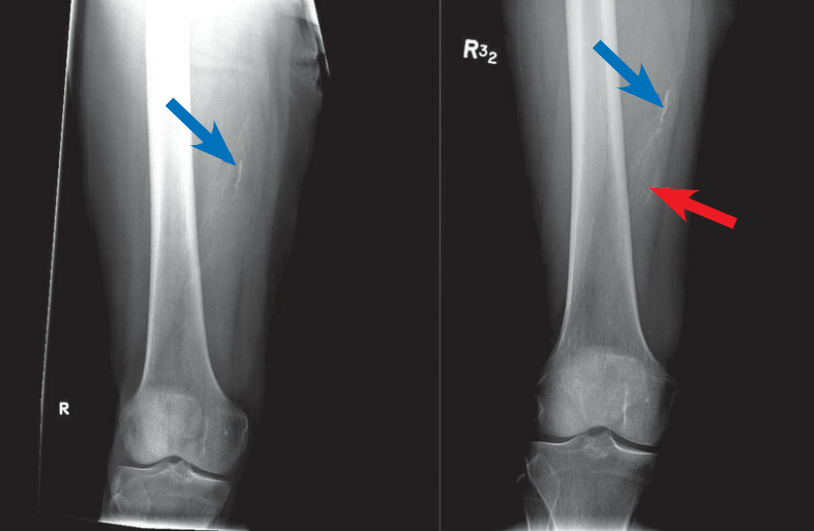

CT 检查:左图异位骨化最初表现为软组织肿块,周围组织水肿,肿块充血周边密度增高,右图患者 4 个月后复查可见局部软组织机化变厚,肿块较前减小但周围见环样骨化。